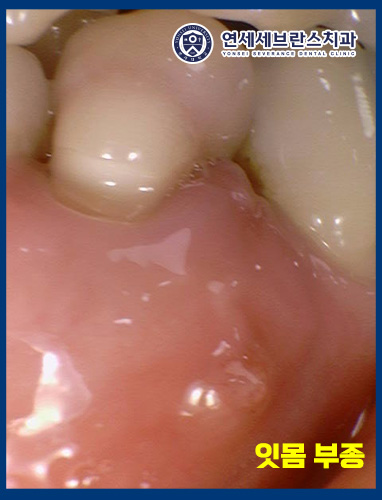

또한 해당 부위 잇몸에는

부종이 동반되어 있었습니다.